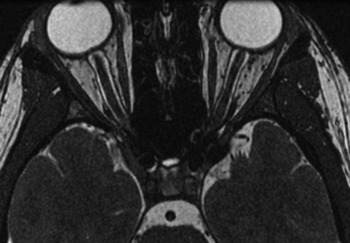

Magnetic resonance imaging (MRI) brain and venogram showed dilatation of the optic nerve sheaths bilaterally with bilateral stenosis of the distal transverse and sigmoid sinuses, no intracranial masses or venous thrombi (Figure 2). Lumbar puncture opening pressure was 28 cm H2O. CSF studies were normal.

Figure 2: Case 2 Axial T2-weighted image demonstrates dilatation of the optic nerve sheaths and flattening of the posterior aspect of the globes.

It has been postulated that age-related loss of compliance in the lamina cribrosa contributes to asymmetric papilledema. Reference Lepore3 Supportively, Bidot’s study of 20 IIH patients with very asymmetric papilledema found a significant association between older age and asymmetric presentation. Reference Bidot, Bruce, Saindane, Newman and Biousse7 As demonstrated in the MRI from Case 2, the optic nerve sheaths were distended bilaterally, which may suggest that variable compliance in the lamina cribrosa mitigates pressure transmission to the optic nerve head. It has also been proposed that microscopic nerve sheath anomalies and variations in the trabecular meshwork Reference Killer, Laeng, Flammer and Groscurth8 might contribute to differences in CSF pressure transduction even when nerve sheath diameters are not significantly different when measured on CT or MRI. Reference Huna-Baron, Landau and Rosenberg2